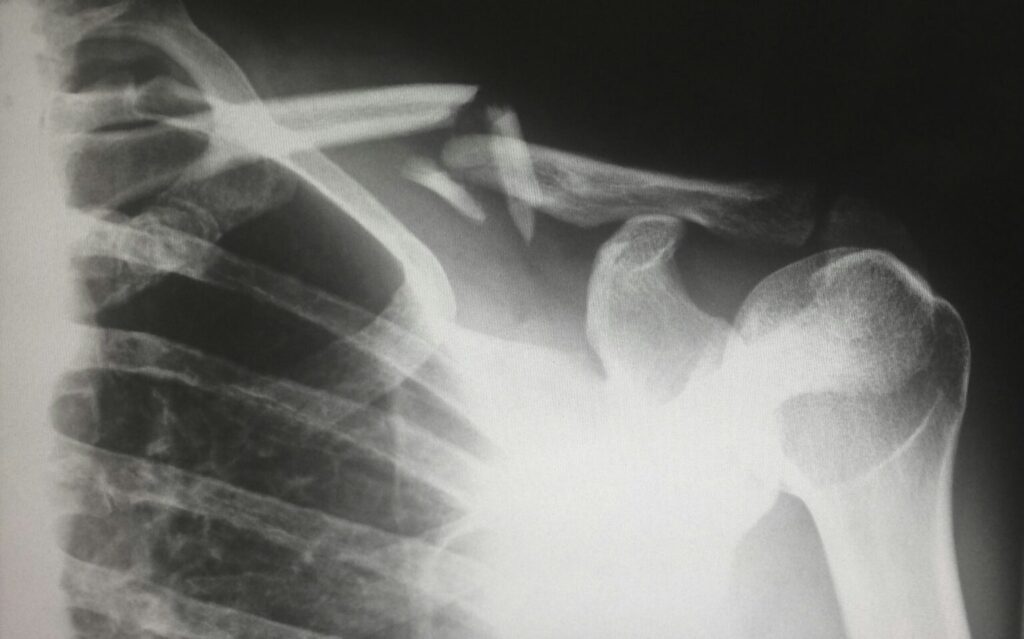

Οι απλές ακτινογραφίες είναι απαραίτητες για να εντοπίσουν  την ακριβή θέση του κατάγματος και να καταδείξουν  περισσότερα σχετικά με τη φύση – τύπο του κατάγματος.

Ο Κος Πολυζώης μπορεί επίσης να στείλει τον ασθενή για περαιτέρω ακτινογραφίες όπως για παράδειγμα ολόκληρου του ώμου  για να ελέγξει για επιπλέον τραυματισμούς.

Εάν συνυπάρχουν πολλαπλές κακώσεις, η αξονική τομογραφία (CT) με τρισδιάστατη απεικόνιση 3D είναι η απεικόνιση εκλογής για ευκρίνεια και λεπτομέρεια και για καλύτερο προεγχειρητικό σχεδιασμό ή και ολοκληρωμένη εικόνα του κατάγματος.